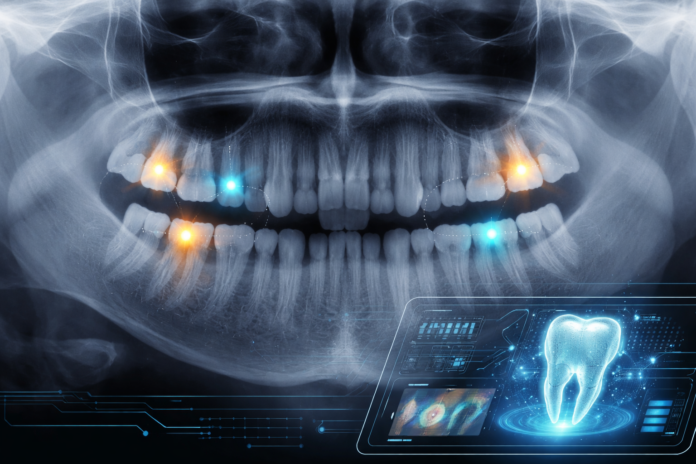

Un estudio publicado en Scientific Reports (2026) desarrolló un modelo de inteligencia artificial con arquitectura transformer para detectar caries en radiografías panorámicas, entrenado con 3.856 radiografías y 12.847 lesiones clasificadas por severidad.

El modelo alcanzó una precisión del 87,3%, con sensibilidad del 81,3% para caries iniciales (D1) y 84,7% para lesiones D2, superando a los modelos anteriores basados en redes neuronales convolucionales.

A diferencia de los sistemas CNN, los transformers analizan simultáneamente detalles locales — cambios sutiles en esmalte o dentina — y el contexto anatómico general del diente, lo que facilita detectar lesiones tempranas que suelen pasar desapercibidas en panorámicas por superposición de estructuras.